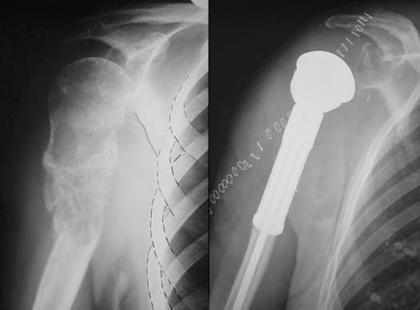

Forty patients who had resection of the proximal humerus for metastatic bone disease and reconstruction with a modular prosthesis were retrospectively reviewed.

Mean functional outcome was 73.1% (Enneking score) and better results were achieved when a reverse prosthesis was implanted. Overall survival was 70% at 1 year, 42.5% at 2 years and 20% at 5 years. Local recurrence occurred in 4 patients, each of whom had initially been treated for a pathological fracture.

回顾性分析了 40 例因转移性骨病而行肱骨近端切除及采用模块化假体重建的患者。

平均功能预后为 73.1%(恩内金评分),使用反置假体的预后更好。1 年生存率为 70%,2 年生存率为 42.5%,5 年生存率为 20%。4 例患者发生局部复发,均为最初因病理性骨折而接受治疗的患者。